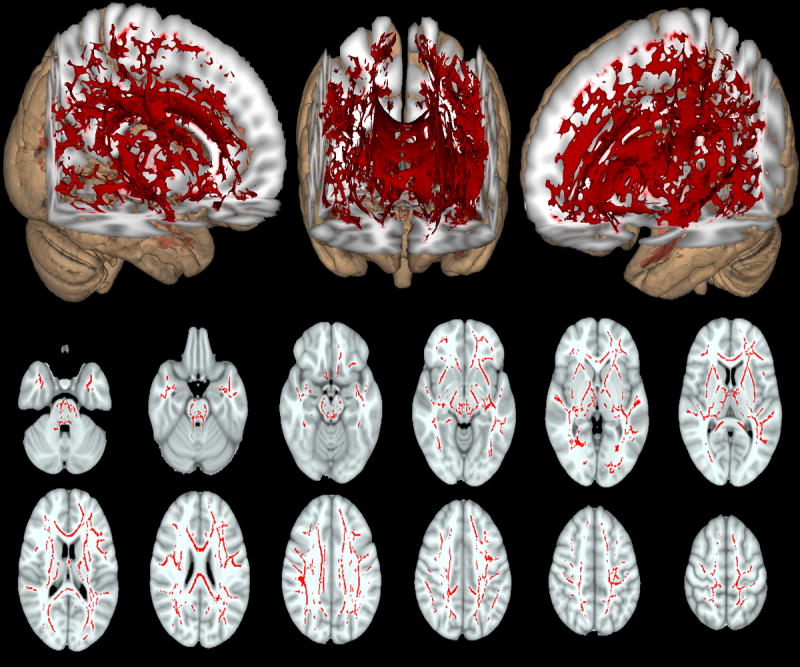

Cellularity was the only isotropic measure that was significantly different between the two groups (p<0.05 corrected). Differences in cellularity were seen diffusely throughout the brain (Figure 2). Due to the large age difference between our two populations we repeated this voxel-wise analysis on a smaller subset of 40 HIV- and 40 HIV+ individuals that were age-gender matched (Supplemental Figure 2). Similar diffuse changes were seen with HIV+ participants having higher cellularity than HIV- individuals. Observed differences between the two diffusion methods may reflect that DTI measures are confounded by isotropic patterns of diffusion that appear as a loss in white matter integrity.

Figure 2.

Differences in cellularity between HIV infected (HIV+) compared to HIV uninfected (HIV-) controls (red voxels). Higher cellularity was diffusely seen in HIV+ patients compared to HIV- controls after controlling for differences in age and gender between the two groups. Overall, diffuse increases in cellularity were seen for both 3D representation (top row) and select 2D axial slices (middle and bottom rows). Significant voxels were corrected for age and gender (p<0.05).